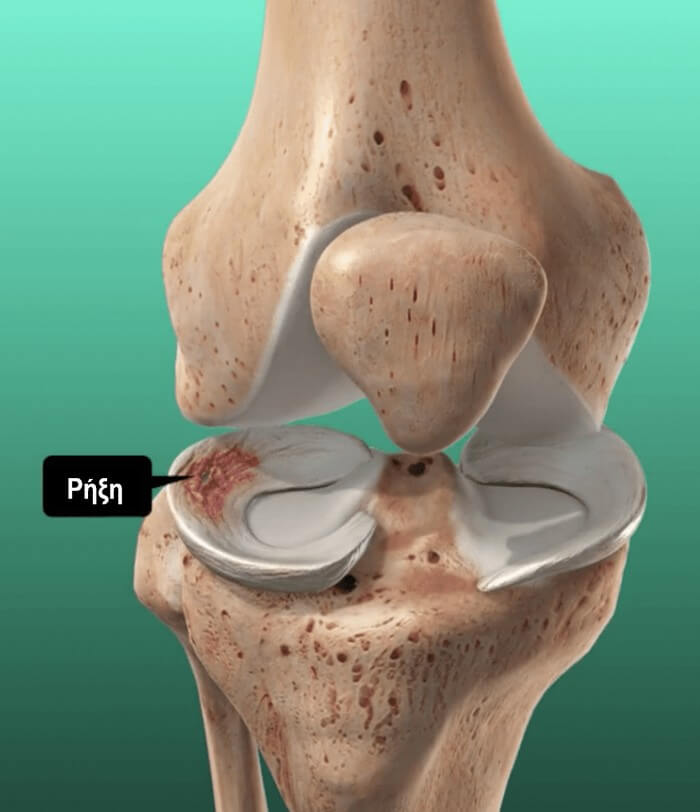

Οι μηνίσκοι (έσω και έξω) είναι δύο ινοχόνδρινοι, ημισεληνοειδούς μορφής, σχηματισμοί, οι οποίοι βρίσκονται στην άρθρωση του γόνατος, μεταξύ του μηρού και την κνήμης.

Βοηθούν στην απόσβεση των κραδασμών όταν βαδίζουμε ή αθλούμαστε αλλά και στην ελαχιστοποίηση της τριβής μεταξύ των οστών της περιοχής.

Διάγνωση Ρήξης Μηνίσκου

Καταρχάς, ο ίδιος ο ασθενής καταλαβαίνει ότι έχει έναν σοβαρό τραυματισμό, αφού παρουσιάζει έντονο πόνο, οίδημα, αστάθεια στο γόνατό του και δυσκολία στην κίνηση και στη βάδιση. Μπορεί επίσης να εμφανιστεί συλλογή υγρού στην άρθρωση (ύδραρθρο) ή ο ασθενής να αισθάνεται ότι η άρθρωσή του “κλειδώνει” σε κάποια συγκεκριμένη θέση.